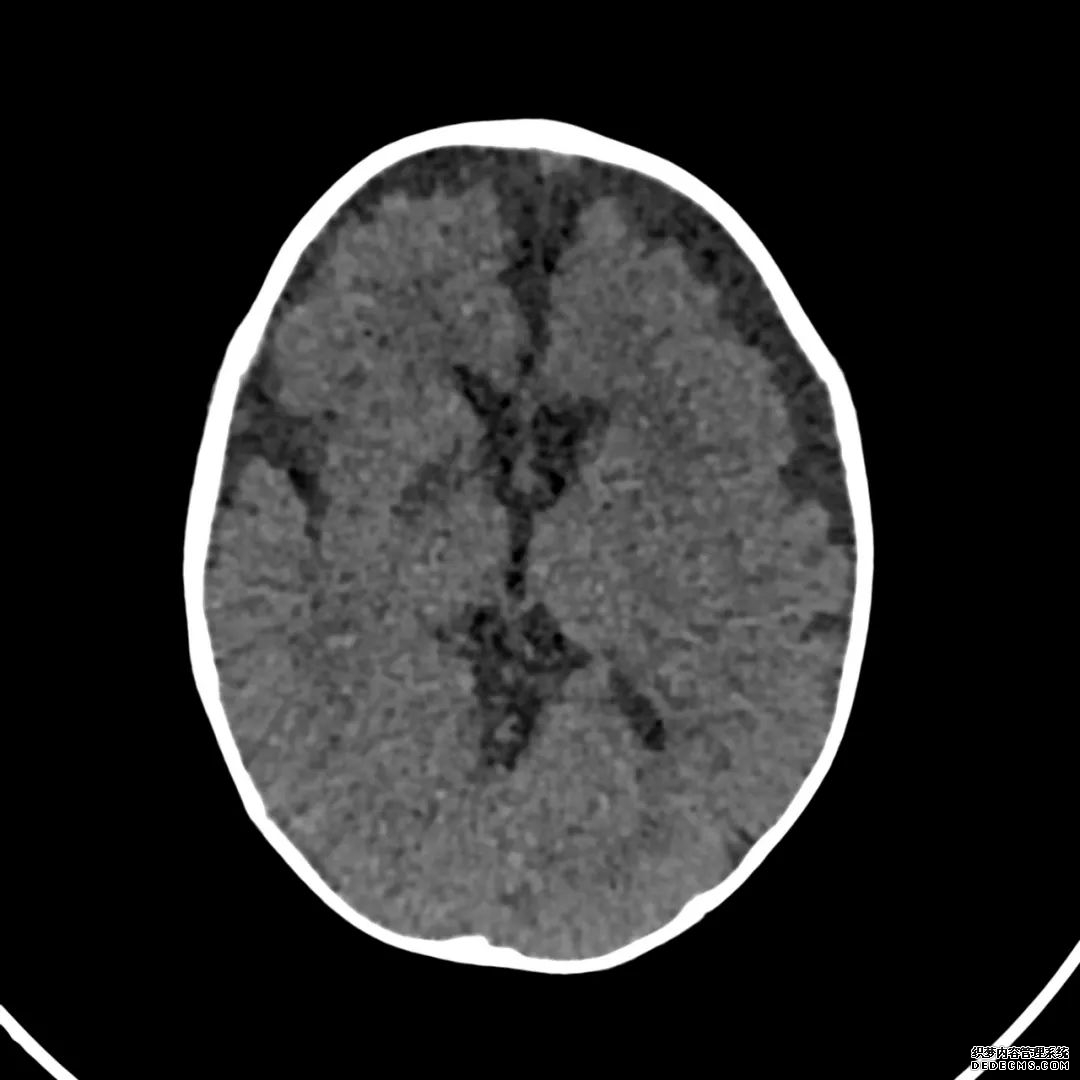

脑部CT检查显示扁豆状核内有略对称的低密度区。

脑MRI显示尾状核、扁豆状核和脑梗头部T2/FLAIR呈双侧对称异常高信号。扩散限制涉及这些区域,其特征是扩散加权DWI(B-1000)上的高强度,ADC图上相应的减弱强度。

印象:通过将这些成像模式与临床和实验室检查结果相结合,就有可能得出低血糖性脑病。